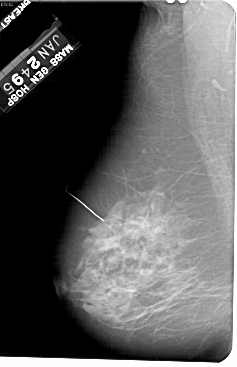

A_1236_1.LEFT_MLO

LEFT_MLO LINES 5491 PIXELS_PER_LINE 3541 BITS_PER_PIXEL 12 RESOLUTION 43.5 NON_OVERLAY

FILE: A_1236_1.RIGHT_MLO.OVERLAY

TOTAL_ABNORMALITIES 1

ABNORMALITY 1

LESION_TYPE CALCIFICATION TYPE PLEOMORPHIC DISTRIBUTION CLUSTERED

LESION_TYPE MASS SHAPE IRREGULAR MARGINS SPICULATED

ASSESSMENT 5

SUBTLETY 5

PATHOLOGY MALIGNANT

TOTAL_OUTLINES 1

BOUNDARY